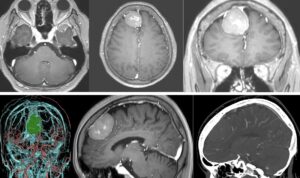

越前市中村病院のご高配により、神の手と称賛される世界的脳神経外科医の福島孝徳先生と、今年6月から福井で手術ができるようになり、直接指導を受けることとなりました。福島先生が最も得意とする聴神経腫瘍の手術を行いました。体位、頭部固定、皮膚牽引、吸引管の持ち方、ポイントサクション、ポイント凝固など一つ一つ注意され、まだまだ勉強しないと痛感しました。腫瘍はとても出血しやすく、また顔面神経の反応も最初から鈍かったため、無理のない範囲での摘出になりました。聴神経腫瘍は全摘出すると顔面神経が切れてしまうので、顔面神経ギリギリでやめるか、ある程度残すか、などの判断に経験が必要で、ワンパターンの摘出は極めて危険です。

福島孝徳先生と中村病院(越前市)で聴神経腫瘍28mmの手術を行いました。